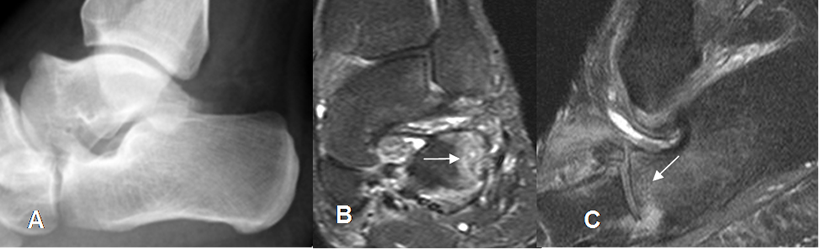

Fig 31. Contusión del calcáneo.

A: Rx lateral, sin hallazgos anormales.

B: RM coronal y C: RM sagital en STIR. Zona hiperintensa en la parte anterolateral del calcáneo, compatible con contusión.